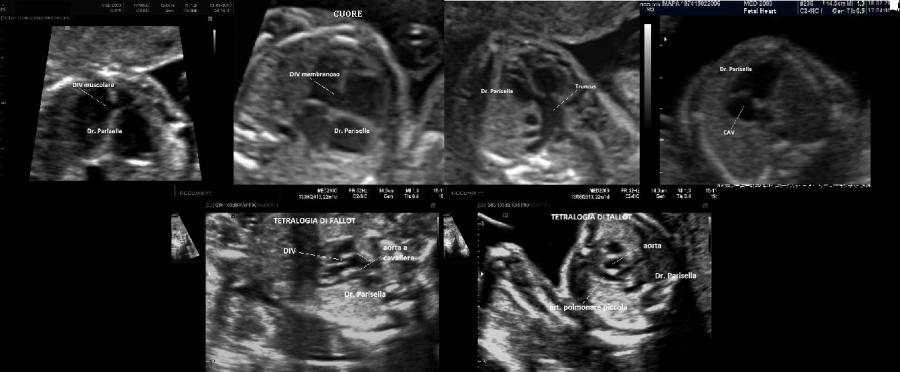

cardiopatie congenite: DIV, Fallot, Traspposizione dei Grossi Vasi

C) Cardiopatie: DIV, Tetralogia di Fallot, Trasposizione dei grossi vasi,

3) cardiopatie congenite (DIV, Fallot, TGV);